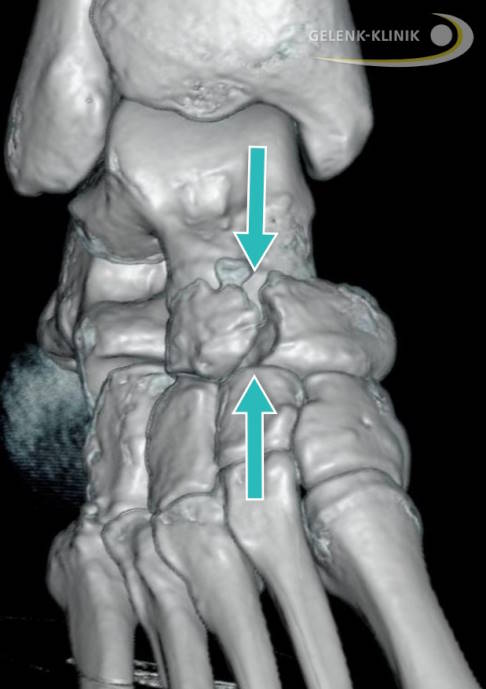

Das Kahnbein zeichnet sich anatomisch durch verschiedene Besonderheiten aus. Es ist der Schlussstein des Fußlängsgewölbes und hat Kontakt zu den Keilbeinen und dem Würfelbein sowie in Richtung zum Körper zum Sprungbein (Talus). Je nach Stellung und Belastung verteilt das Kahnbein sehr spezifisch die Kraft auf das Fußgewölbe. Fehlstellungen des Fußes können somit zur Entwicklung einer Stressfraktur des Kahnbeins beitragen. Ermüdungsbrüche des Kahnbeins verlaufen immer längs der Fußachse, aber quer durch den Kahnbeinknochen. Hier ist die Durchblutung am schlechtesten, weshalb der Knochen in diesem Bereich am wenigsten gegen Überlastung reagieren kann.

Beim Verdacht auf einen navikulären Ermüdungsbruch wird die Bildgebung eingeleitet. Meist führt man zunächst eine belastete Röntgenaufnahme einschließlich Schrägaufnahme durch. Allerdings sind Röntgenbilder oft erst einmal negativ. Hilfreicher ist die digitale Volumentomographie (DVT). Mit ihr lassen sich Frakturlinien besser erkennen und auch Fissuren, also winzige Risse im Knochen, gut darstellen. Eine kernspintomographische Untersuchung (MRT) ist ebenfalls möglich, bei deutlichem klinischem Verdacht aber nicht unbedingt erforderlich. Die MRT kann jedoch helfen, wichtige Differenzialdiagnosen auszuschließen.

Eine besonders wichtige Differenzialdiagnose ist das zweigeteilte Kahnbein (Os naviculare bipartitum). Es lässt sich in der Regel sowohl in Röntgen- als auch auch in CT- und MRT-Aufnahmen gut erkennen. Für das zweigeteilte Kahnbein spricht, wenn das verdächtige Knochenteil oder -fragment abgerundet ist. Auch die Unterscheidung zwischen einer akuten Fraktur und einem Ermüdungsbruch ist in der Bildgebung möglich. So zeigt z. B. die Stressfraktur im Gegensatz zum akuten Bruch oft eine stärkere Sklerosierung. Eine weitere Differenzialdiagnose ist die Osteonekrose des Kahnbeins, das Müller-Weiss-Syndrom.

Verschobene Frakturen bedürfen einer frühzeitigen offenen Reposition und einer zusätzlichen Fixierung. Der Zugangsweg für die Operation ist am Fußrücken. Die Zugschraube bringt der Chirurg durch das kleinere, meist äußere Fragment in das größere, innen liegende Fragment ein. Sollte ein Zwischenraum (Diastase) verbleiben, wird dieser vom Chirurgen mit autologem Knochenmaterial gefüllt. Dadurch lässt sich die mechanische Stabilität verbessern.